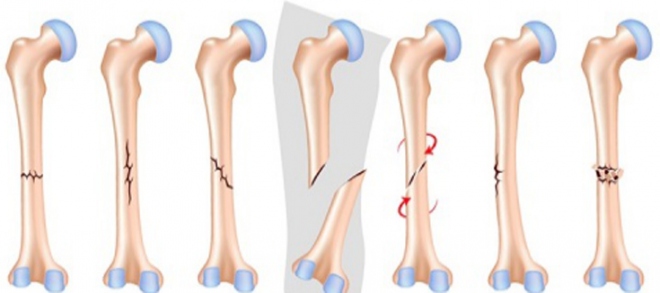

Τα κατάγματα της διάφυσης του μηριαίου είναι συνήθως κατάγματα επισυμβαίνοντα σε ατυχήματα εργατικά ή τροχαία και αφορούν άτομα νεαρής ηλικίας. Στους υπερήλικες το μηριαίο, όπως ανεφέρθη, σπάει στην περιοχή των τροχαντήρων.

Το κάταγμα του μηριαίου είναι διακοπή της συνεχείας του μηριαίου οστού, που είναι όπως έχει αναφερθεί ένα αυλοειδές οστούν.

Ο φλοιός των αυλοειδών οστών είναι πολύ ισχυρός και γι΄ αυτό τα κατάγματα στα αυλοειδή οστά, είναι αποτέλεσμα μεγάλης βίας.

Το κάταγμα της διάφυσης του μηριαίου προκαλεί, όπως και στο βραχιόνιο, εκτός του πόνου και της τοπικής διόγκωσης, παρά φύσιν κίνηση στη μεσότητα του μηρού, που επιδεινώνει τον πόνο και προκαλεί κριγμό.